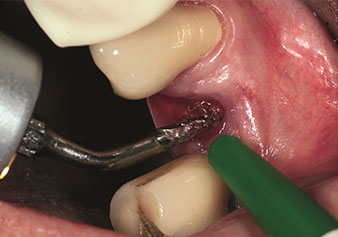

Situazione in seguito a estrazione con piezochirurgia

Fig. 2: Situazione in seguito a estrazione con piezochirurgia.

Foto: © Dott. Torsten Conrad (Bingen am Rhein)

Un’applicazione che viene spesso sottovalutata è l’estrazione atraumatica di radici di denti o frammenti di radici nell’ambito della gestione alveolare. I periotomi sottili, che sono attualmente disponibili in due versioni (EX1 ed EX2 di W&H), possono essere, inoltre, utilizzati per rimuovere con facilità denti che hanno precedentemente subito uno specifico trattamento endodontico o con radici anchilosate. Ne consegue l’estrazione di alveoli in cui i tessuti duro e molle sono entrambi completamente intatti in quanto è generalmente possibile evitare la riflessione.

Ciò pone le basi ottimali per un trattamento con impianto immediato o successivo (Figure 1 e 2 inserite grazie alla gentile concessione del Dott. Torsten Conrad, Bingen a. Rhein).